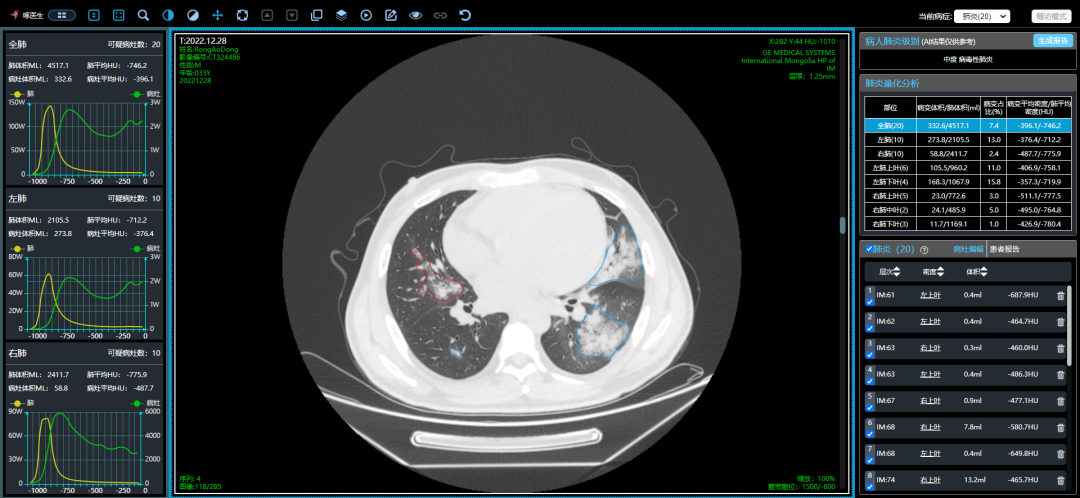

近期,多地醫(yī)生發(fā)現(xiàn)患者出現(xiàn)肺炎或白肺癥狀,引發(fā)關(guān)注。那么什么是白肺呢?其實白肺是肺部影像學(xué)表現(xiàn)的一個口語化描述。當(dāng)出現(xiàn)炎癥和感染,肺泡被滲出液等填充,在影像學(xué)上的表現(xiàn)就是出現(xiàn)白色區(qū)域。并不是只要肺部出現(xiàn)了炎癥就都叫白肺,一般來講肺部炎癥較重、滲出液較多,白色的影像區(qū)域面積達(dá)到70%?80%時,在臨床上把它稱為白肺。通過“啄醫(yī)生”可以準(zhǔn)確地識別新冠肺炎的典型白肺影像,以下選取幾例最新病例加以說明。

從這3個確診新冠肺炎呈“白肺”病例來看,“白肺”多見于老人、兒童以及帶有基礎(chǔ)病的新冠患者,病灶可發(fā)生在肺內(nèi)任何肺葉,病灶形態(tài)特點也是多樣化,符合病毒性肺炎的影像表現(xiàn)。從影像學(xué)角度出發(fā)重點在于快速評估病情,提升人工讀片的客觀性。 “啄醫(yī)生閱片機器人??新冠肺炎CT影像輔助分診與評估系統(tǒng)”可以準(zhǔn)確地識別新冠肺炎的典型影像表現(xiàn)如雙肺外周胸膜下多發(fā)的磨玻璃影、小葉間隔增厚或合并鋪路石征等,對于部分患者由于影像表現(xiàn)早于臨床癥狀,更具有早期發(fā)現(xiàn)、早期診斷的優(yōu)勢。